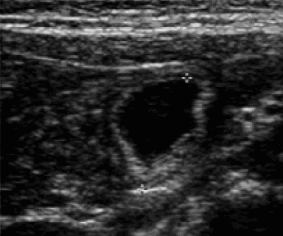

| Image d'une masse liquidienne

delimitee par une paroi digestive . Imege

echoraphique de diverticule de Meckel . |